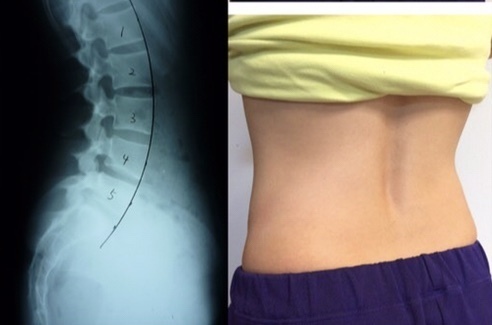

反り腰の腰痛は真ん中にくぼみができる

反り腰は腰の筋がギューと収縮して腰がそっている。

反っている腰椎の関節の動きを作り、反りを減らしていく事が次の課題になります。

腰が反る腰痛解消には関節の動きを変える

腰が反っている状態からフラットにする必要があります。